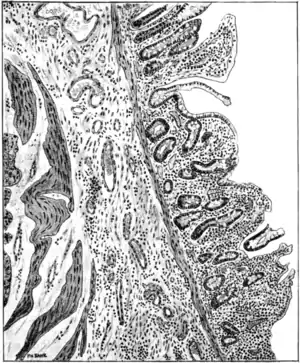

Fig. 83.—Transverse section of ileum in case of sprue, showing partial loss of columnar epithelium (probably a post-mortem change), shrinkage of villi, round-cell infiltration, fibrosis of submucosa, and dilatation of nutrient vessels of submucosa. (Bahr.)

anus, either in patches or universally, is superficially eroded and interstitially atrophied. The internal surface of the bowel is coated with a thick layer of dirty grey, tenacious mucus containing numerous yeast

cells and branching mycelium (Bahr), which conceals patches of congestion, of erosion, or even of ulceration, besides such evidences of similar antecedent disease as pigmented areas and thin-scarred, cicatricial patches. The villi and glands are eroded and in many places completely destroyed. Here and there minute